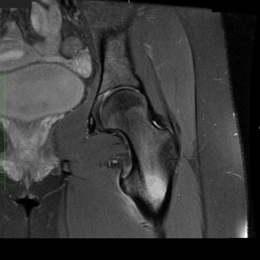

- • Scans include X-ray, CT, MRI, Bone scans. When it is very small and only a few millimeters it can be difficult to see on an Xray and MRI. The MRI usually shows extensive swelling around the tumor that can make it difficult to see the actual tumor on the MRI.

Radiographic imaging is used to help form a diagnosis. These include X-Ray, MRI, CT and Bone Scans.

An example of an osteoid osteoma is shown.